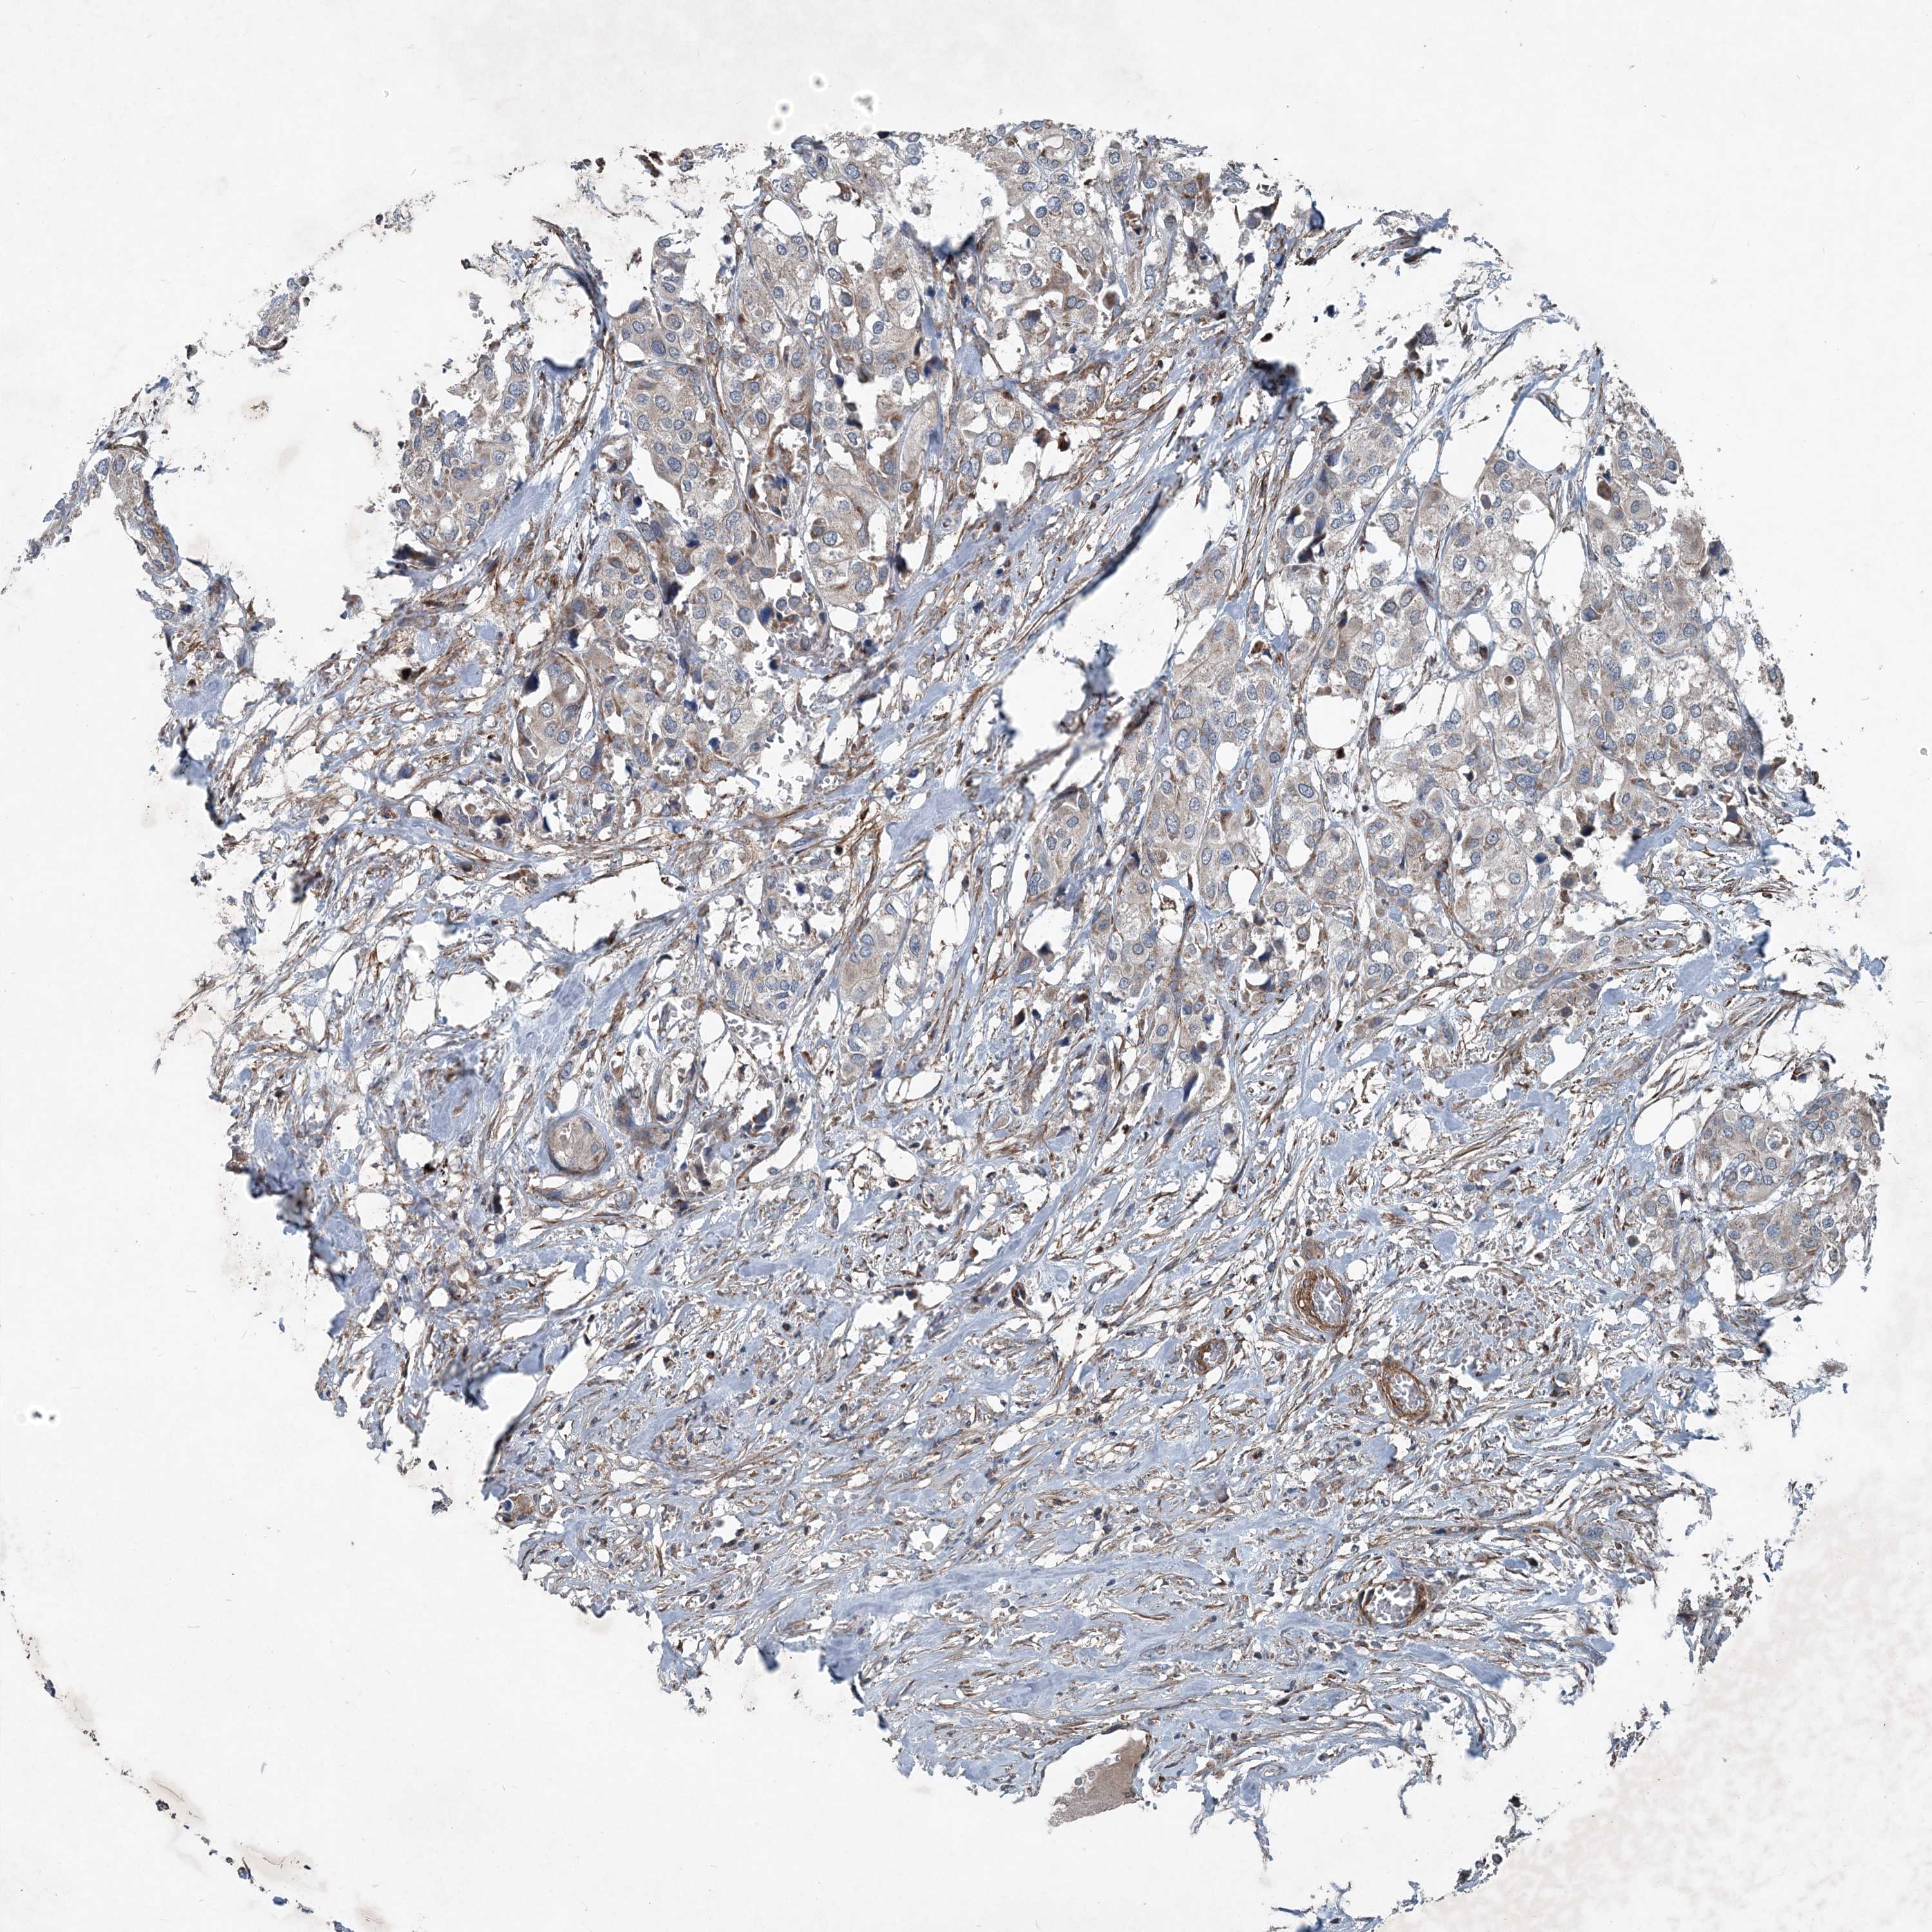

UROTHELIAL CANCER - Protein expressioni

A mouse-over function shows sample information and annotation data. Click on an image to view it in a full screen mode. Samples can be filtered based on level of antibody staining by selecting one or several of the following categories: high, medium, low and not detected. The assay and annotation is described here.

Antibody stainingi

Antibody staining in the annotated cell types in the current human tissue is reported as not detected, low, medium, or high, based on conventional immunohistochemistry profiling in selected tissues. This score is based on the combination of the staining intensity and fraction of stained cells.

Each image is clickable and will lead to virtual microscopy that enables deeper exploration of all samples and also displays staining intensity scores, fraction scores and subcellular localization as well as patient and tissue information for each sample.

Antibody HPA035933

Staining

High

Medium

Low

Not detected

Intensity

Strong

Moderate

Weak

Negative

Quantity

>75%

75%-25%

<25%

None

Location

Nuclear

Cytoplasmic/membranous

Cytoplasmic/membranous,nuclear

Urothelial carcinoma, High grade